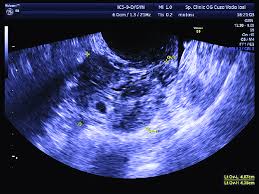

Transvaginal Ultrasound From A 28 Year Old Woman With A Left Ectopic Download Scientific Diagram